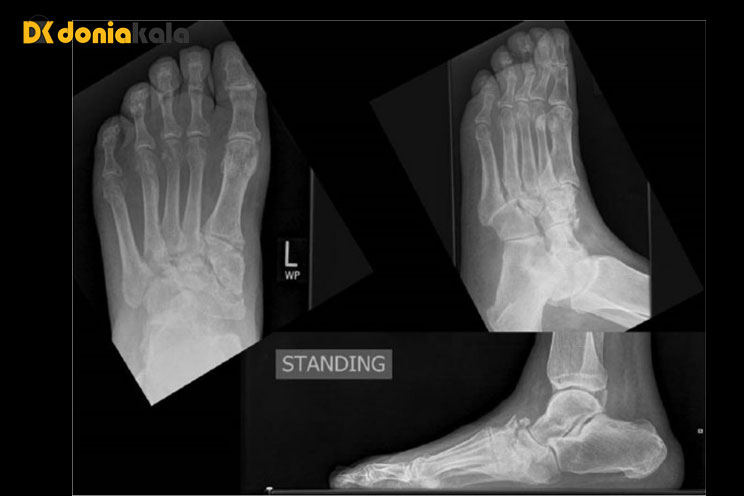

جراحی برای آن دسته از بیمارانی که دارای ناهنجاری های شدید مچ پا و پا هستند که ناپایدار هستند و در معرض خطر بالای ایجاد زخم پا هستند توصیه می شود. علاوه بر این، اگر تغییر شکل استفاده از بریسها و ارتزها را دشوار کند، ممکن است جراحی نشان داده شود. پس از جراحی، بیمار باید برای مدت طولانی از قرار دادن وزن کامل روی پای شارکو خودداری کند. همه افراد مبتلا به پای شارکو باید تا آخر عمر خود را به پوشیدن کفش های محافظ و مراقبت بیشتر از پاهای خود اختصاص دهند. آموزش بیمار و اعضای خانواده در مورد مراقبت های پیشگیرانه از پا و علائمی که باید مراقب آنها بود، بخش مهمی از پیشگیری از مشکلات آینده است.

تغییر شکل در هر قسمت از پا یا مچ پا می تواند باعث ایجاد زخم های پوستی از فشار استخوان به کفش یا زمین شود. هنگامی که پای شارکو مچ پا را تحت تاثیر قرار می دهد، مفصل ممکن است ناپایدار یا "فلاپی" شود زیرا بافت جایگزین استخوان در مفصل شده است. این به اصطلاح "پا فلاپی" نیز می تواند باعث ایجاد زخم شود. زخم ها اغلب به دلیل عوارض دیابت، گردش خون ضعیف در پاها، ماندن طولانی مدت روی پاها و ایجاد عفونت ها دشوار است. زخم عفونی که بهبود نمی یابد می تواند اندام را تهدید کند و حتی منجر به قطع پا یا حتی ساق پا شود.